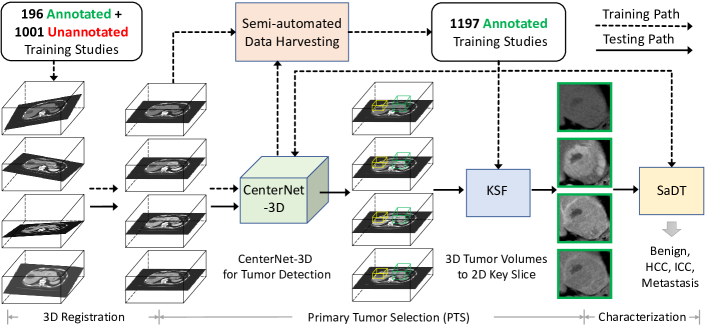

Method. Specifically, we (1) propose a fully automated end-to-end framework, and also (2) can train and test our approach on a scalable and partially-annotated dataset of 1305 multi-phase \acCT studies/patients, all with histopathological ground truth. To accomplish this, we articulate several modules within the framework. A key module is a 3D generalization of the CenterNet model [21] to both curate our data and also detect liver tumors in deployment. Our data curation workflow boostraps off of existing large-scale public liver lesion cohorts [22, 23], along with manually annotated cases from our own dataset. This allows us to effectively exploit larger-scale hospital imaging data via semi-automated annotations. With all curated training data from both public and private sources in hand, we then execute classification in two stages. In the first stage, \acPTS uses the aforementioned 3D tumor detector and a\acKSF, trained using our curated data, to filter and select \acROI proposals for primary tumor slices. The second stage employs \acSaDT, an analysis pipeline we develop to precisely model and differentiate the visual appearance on these primary tumor slices. This provides a determination of the lesion type. To the best of our knowledge, we are among the first studies to represent the task of radiological liver lesion characterization as a dynamic deep texture learning problem111As discussed in [24], the primary imaging based cancer diagnosis cues are the potential tumor’s size, shape and texture information..

Fig. 2 illustrates our overall workflow.

For pre-processing, we register all non-venous phase \acCT scans of the same patient to the venous phase using DEEDS [48] and apply phase detection [49] to identify each scan’s contrast phase. Our 3D tumor detection model (Sec. II-A) performs as the backbone module to facilitate both data harvesting (Sec. II-B) and \acfPTS (Sec. II-C), followed by using \acSaDT to classify primary \acpROI extracted by \acPTS (Sec. II-D).